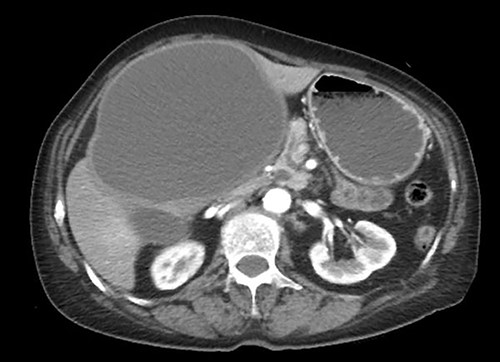

A 75-year-old bedridden woman presented to our hospital with chief complaints of epigastric pain, anorexia and a palpable mass in the epigastric region. She had a history of surgery for meningioma, but no history of abdominal surgery. Ultrasonography revealed a well-defined large cystic lesion with a long diameter of approximately 150 mm in the left liver lobe. Contrast-enhanced computed tomography showed a giant hepatic cyst with an irregular mass in liver segment 4, 20 × 16 cm in size (Fig. 1).

The hepatic cyst compressed the stomach, duodenum, pancreas and gallbladder, and the descending part of the duodenum was difficult to identify because of severe thinning caused by the compression. On magnetic resonance imaging, the giant cyst showed low signal intensity on T1-weighted and high signal intensity on T2-weighted images, and there was a solid component with a high signal on diffusion-weighted images on the dorsal side of the cyst (Fig. 2).